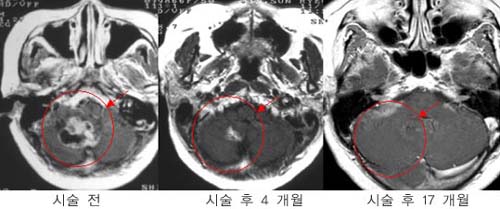

³ú¼ö¸·Á¾

ÅÍŰ¾È

»óºÎ ¼ö¸·Á¾ ȯÀÚÀÇ MRI »çÁø.°¨¸¶³ªÀÌÇÁ

¹æ»ç¼±¼ö¼ú 16°³¿ùÈÄ Á¾¾çÀÇ Å©±â°¡ ÇöÀúÈ÷

°¨¼ÒÇÏ¿´´Ù